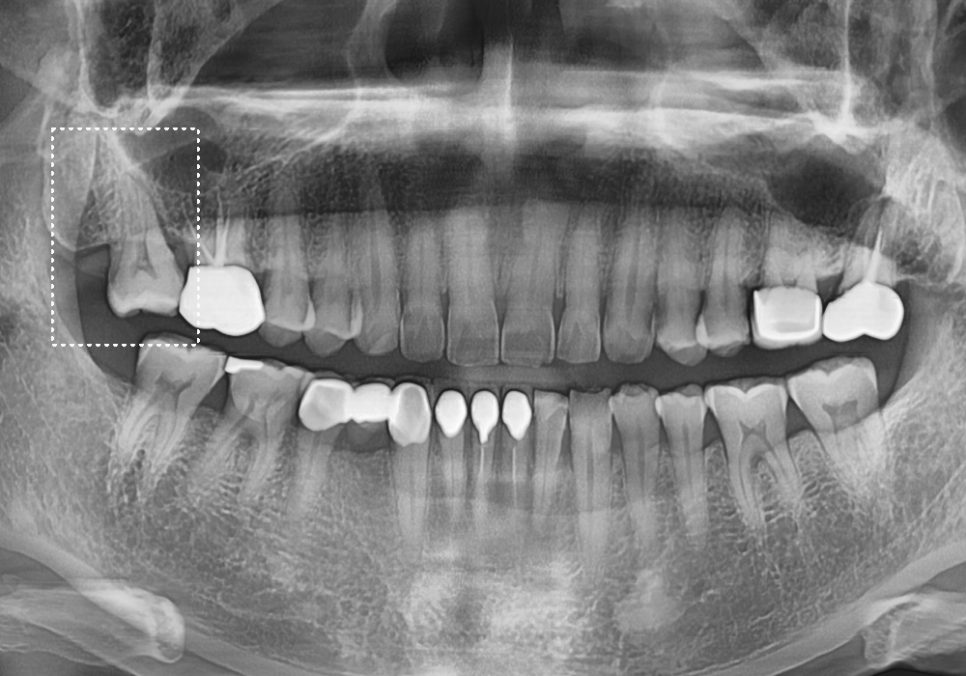

240213

방사선 사진상으로는 다행히 금이

뿌리까지 완전히 내려가지는 않은 것으로 보여서,

환자분과 상의 끝에 자연치아를 살려보기 위한

신경치료를 시작했습니다.